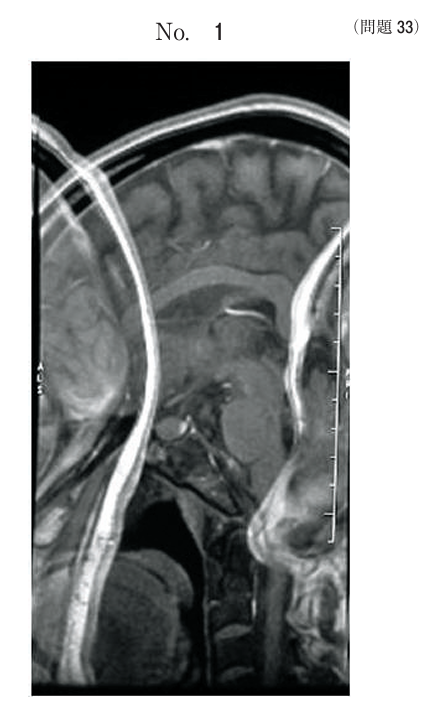

午前/問題33

頭部MR矢状断像において生じるアーチファクトを除去する方法はどれか。

1.加算回数を増やす。

2.位相エンコード数を増やす。

3.受信周波数帯域を拡大する。

4.被検者の体表金属を除去する。

5.検査室の電波シールドを修繕する。